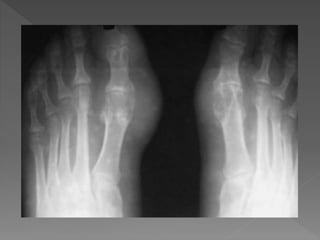

AMERICAN COLLEGE OF RHEUMATOLOGY

radiologicos:

9 Quistes subcondrales sin erosiones a los rayos X.

DIAGNÓSTICO

POR IMAGEN

+ Partes

balndas.

Depositos

tofáceos.

Erosiones

intraarticulares.

Sacabocados,

halo de

esclerosis.